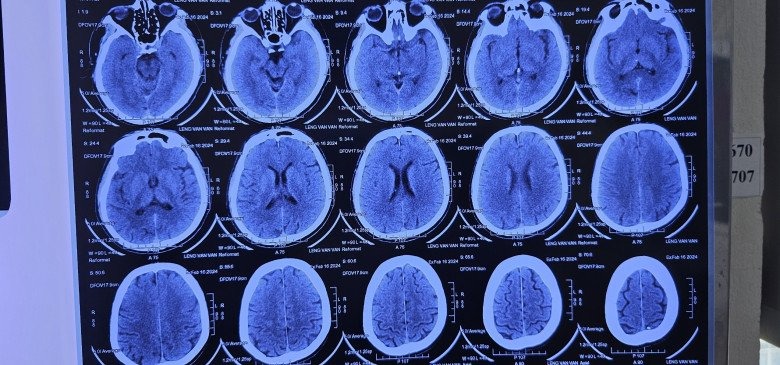

Ngày 20/2, bác sĩ Lê Văn Thiệu, Khoa Nhiễm khuẩn tổng hợp, Bệnh viện Bệnh Nhiệt đới Trung ương chia sẻ với VnExpress, bệnh nhân đến viện khi đau đầu, chóng mặt, buồn nôn, đau mỏi cơ đùi phải. Các triệu chứng xuất hiện trước nhập viện một tuần.

Bác sĩ thăm khám phát hiện người đàn ông nhiễm nhiều loại giun sán, đặc biệt là sán dây. Kết quả chụp X-quang thấy có rất nhiều sán nằm ở các cơ. Bệnh nhân nói có sở thích ăn những món tái, sống như gỏi cá, rau sống và tiết canh. Trước đó, anh đã có 3 đợt điều trị sán cơ và sán não.